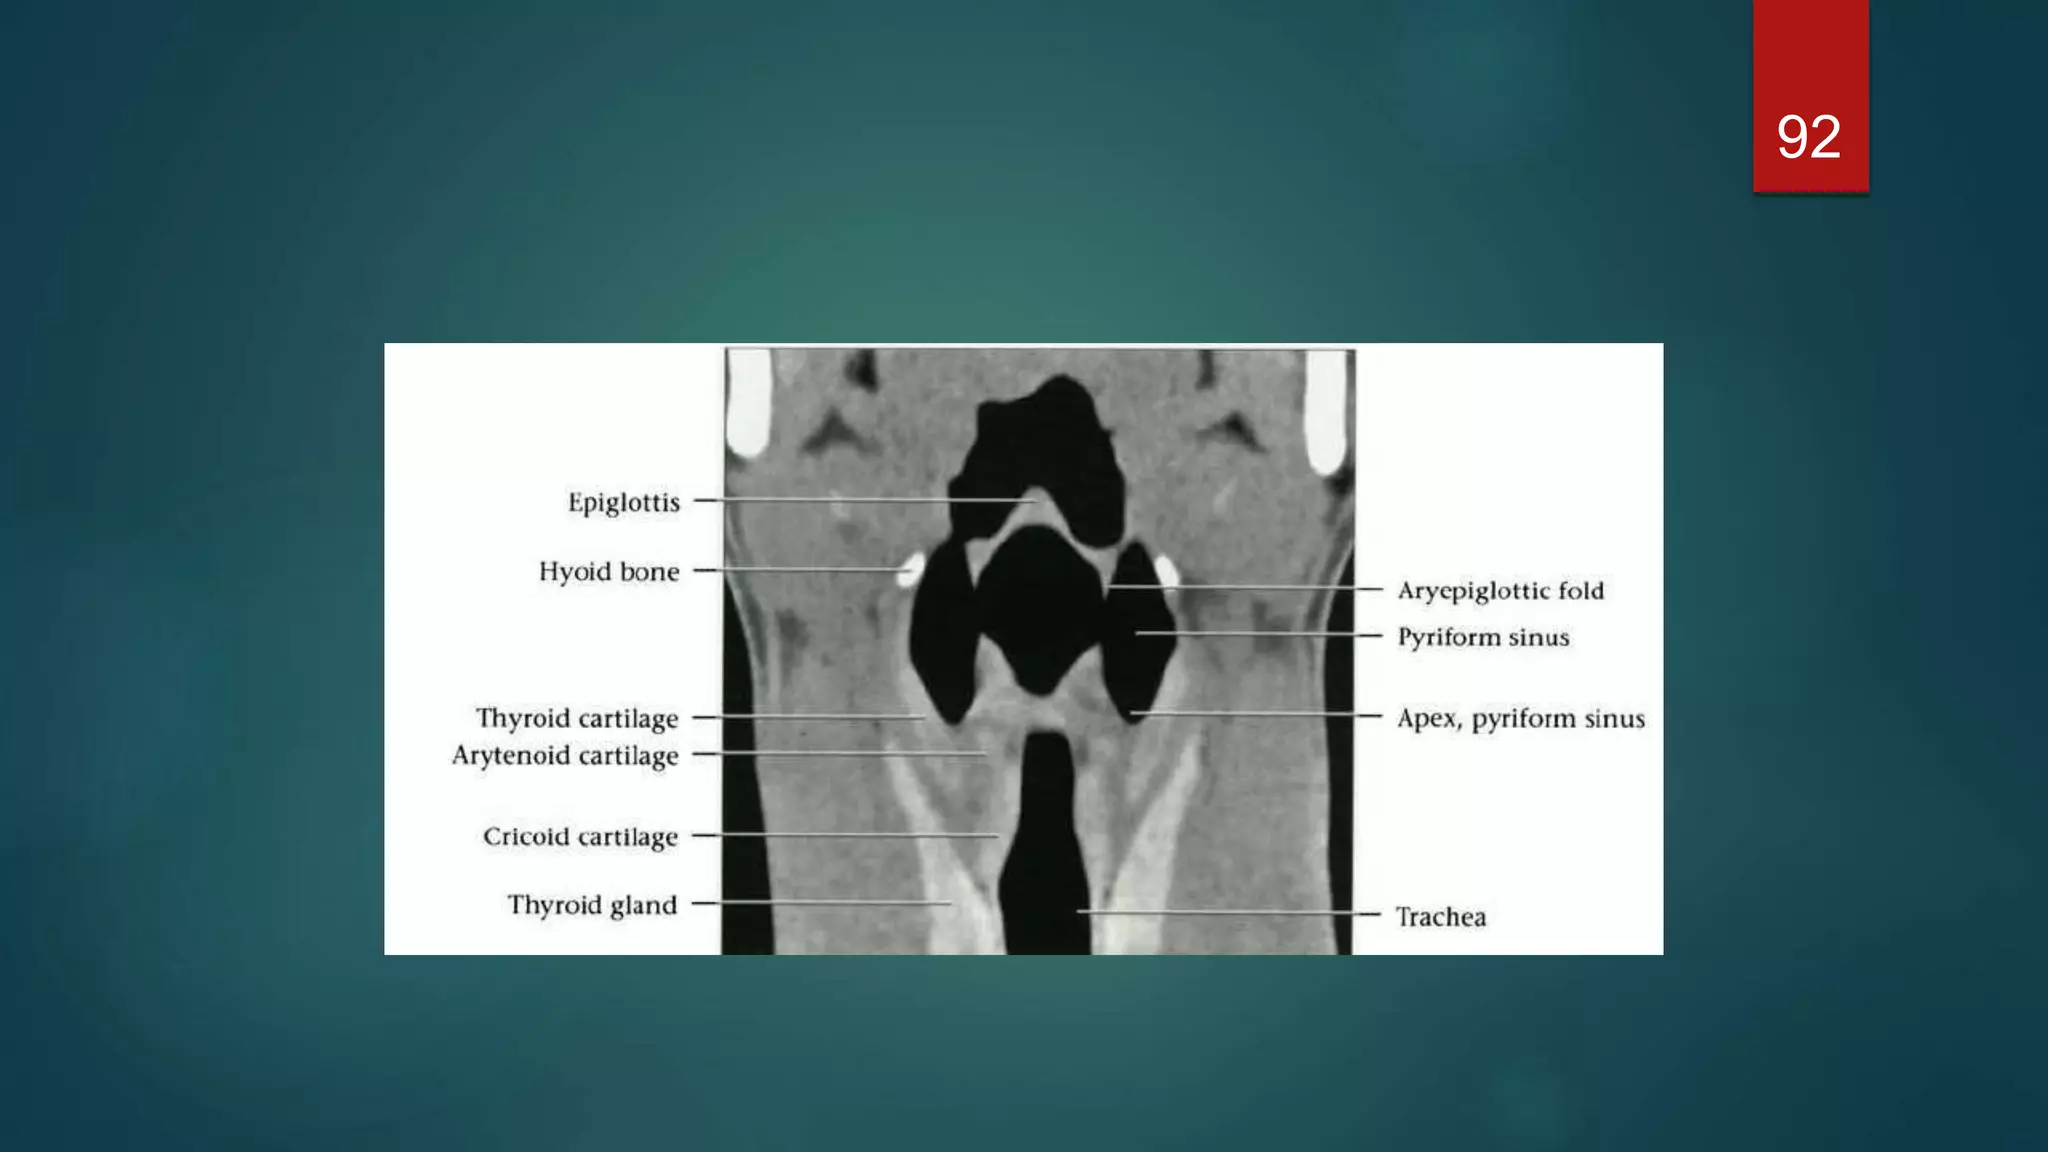

 The epiglottisis a leaf-shaped cartilage whose narrow base is attached to the inner surface of the thyroid cartilage  It projects up behind the base of the tongue and directs boluses laterally into the piriform fossae during deglutition, thus protecting the larynx.  Three mucosal folds, the glossoepiglottic folds - namely, a central and two lateral folds - pass from the anterior surface of the epiglottis to the base of the tongue. These form paired recesses between the base of the tongue and the epiglottis known as the valleculae.  A further pair of mucosal folds pass from the lateral margin of the epiglottis posteriorly to the arytenoid cartilages separating the larynx from the piriform fossae. These are the aryepiglottic folds which, together with the epiglottis, define the entrance to the larynx.  The cavity of the larynx is divided into three parts by upper and lower pairs of mucosal folds. The upper pair of folds are the false cords. The space between the laryngeal entrance and the false cords is known as the vestibule or the sinus of the larynx.  The lower pair of folds are the true cords and contain the vocal ligaments, which are responsible for voice production. The space between the false and true vocal cords is the laryngeal ventricle. 70

Cross-sectional anatomy ofthe larynx Supraglottic level  The larynx is anterior to the piriform sinuses, separated from them by the aryepiglottic folds. 71

92